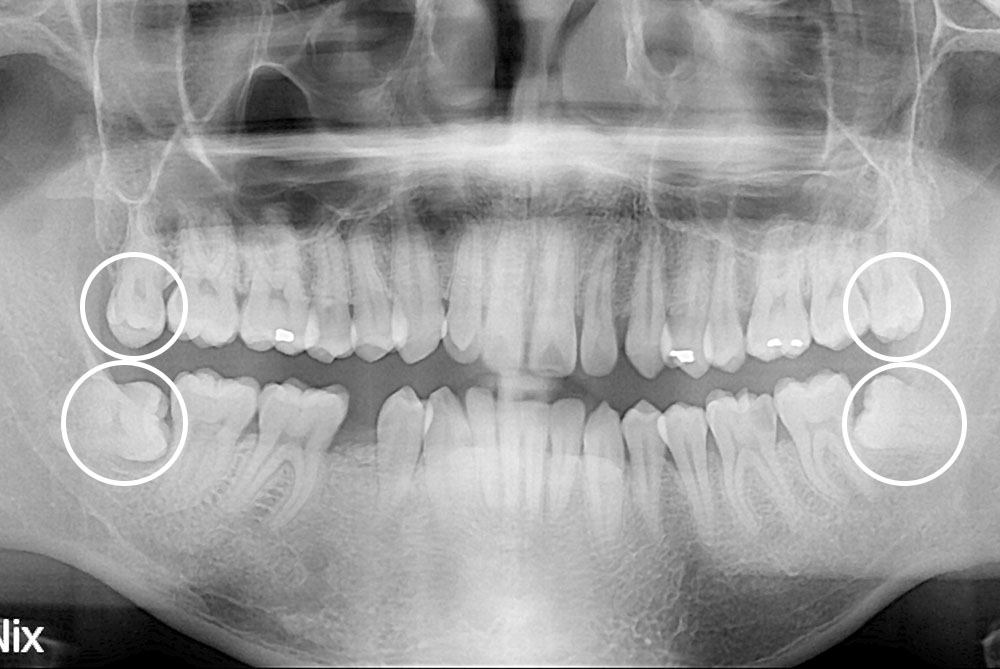

[사랑니] 매복 사랑니 발치

치료전 : 2019-03-11